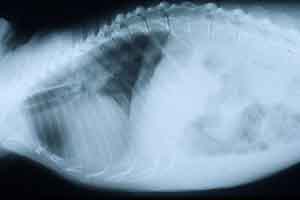

- Case 20-2. CAT scans.

- History: According to the owner, the dog exhibited

three generalized tonic/clonic seizures and behavioral changes

for ten days. The seizures occurred at various times of the day.

Neurologic examination revealed that vision was normal in right

eye and absent in the left eye. Pupillary light reflexes were

lower for this eye. Computed tomography images obtained after

administration of contrast media showed two lesions, one (7 mm

diameter) in the left olfactory lobe and the second (25 mm diameter)

in the right temporal area. Stereotactic biopsy was performed

three days later. Histopathological features revealed an idiopathic

granulomatous encephalitis. The dog was treated by immunosuppressive

therapy. Generalized seizures occurred a few weeks later. Continued

decline resulted in euthanasia.